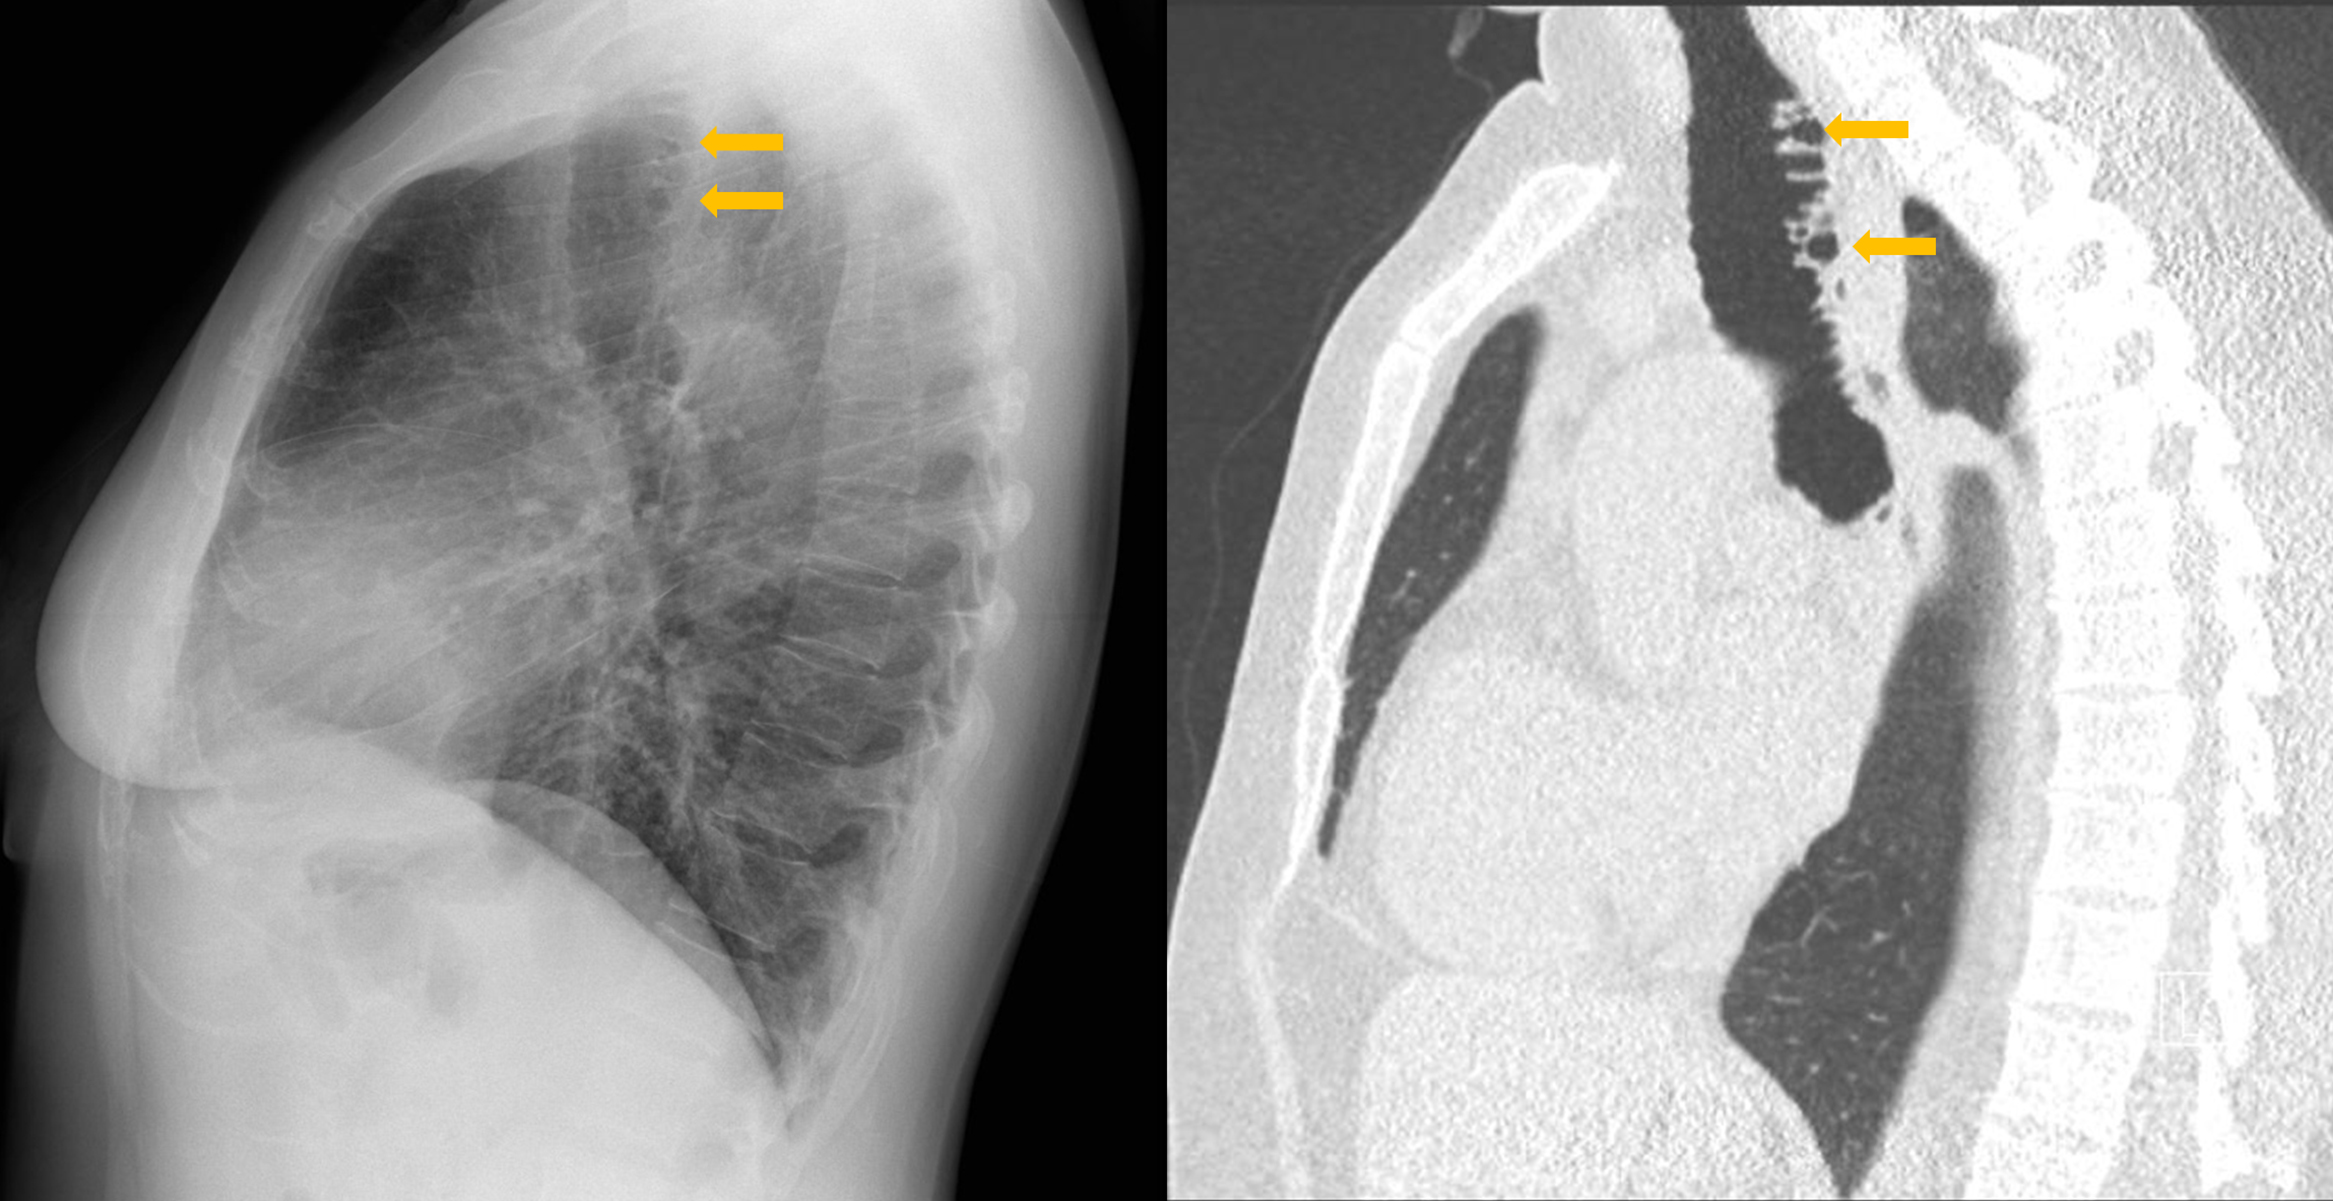

On the lateral chest X‑ray (Figure 2), the tracheal diverticulosis was also observable.

Figure 2

Tracheal diverticulosis: sagital CXR and CT comparison.